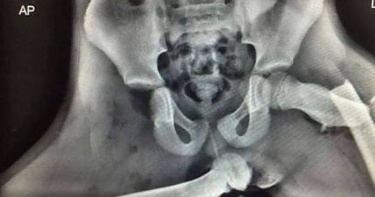

坐副駕習慣翹腳...她遇嚴重車禍「腿骨插進屁股」 驚人X光照片曝

許多人坐在副駕駛座時,會把腳翹在前方置物箱上,覺得這樣比較舒適,但其實這是一個相當危險的動作,一旦發生車禍,後果不堪設想。經常在IG上分享醫療衛生相關案例的帳號「med.index」近日PO出一張X光照片,照片中可以看到兩條大腿骨嚴重骨折,其中一邊的腿骨還插進了屁股,令人看得怵目驚心,而這就是將腳翹在前方置物箱上且發生車禍的後果。IG帳號「med.index」12日PO出一張X光照片,可以看到一邊大腿髖關節骨折,另一邊則是位移戳出皮膚後,再插進了屁股,而造成這樣後果,是因為該名患者把腳翹在副駕前置物箱上,結果發生車禍所致,「這就是為什麼我們永遠不應該把腳放在汽車儀表板上。」貼文曝光後立刻引起熱議,網友紛紛留言「真的無法想像這個的痛苦程度」、「真擔心這個人的生殖器」。據悉,這張X光照的患者是一名英國女子,過去她坐在副駕駛座都會習慣把雙腳放在前方置物箱上,丈夫曾出言勸阻,但她仍維持這樣的習慣,沒想到後來發生了嚴重車禍,當下安全氣囊爆出,猛烈力道導致她的腿骨從髖關節的髖臼上脫落並位移,戳出了皮膚後再插進屁股,之後留下了嚴重後遺症。 View this post on Instagram A post shared by Medical Doctors and Students (@med.index)